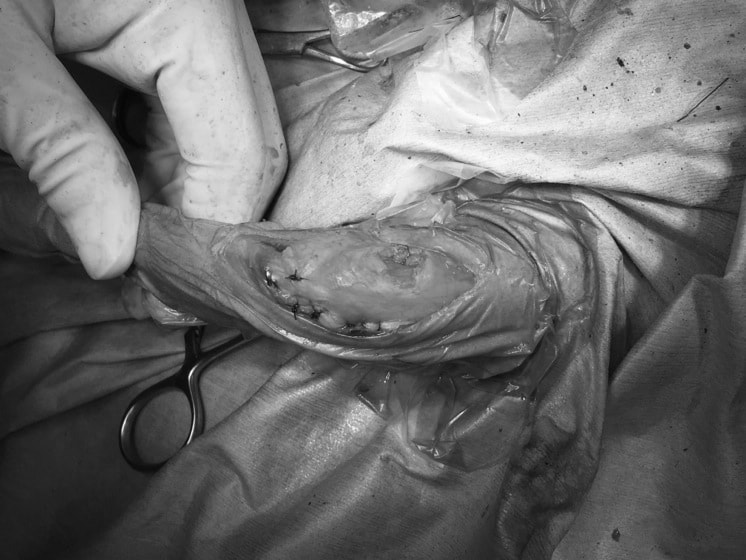

以前から左右後肢の跛行が認められ、整形外科学的検査・レントゲン検査により左右の膝蓋骨脱臼が認められた。症状が重度である左膝の膝蓋骨脱臼整復術を行った。外科手技は縫工筋及び内側広筋の解放、脛骨粗面の外側転位、滑車ブロック形造溝術、内外側関節方の縫縮を実施した。術後一か月時点で、左の膝蓋骨は安定しており経過は良好である。

手技は縫工筋及び内側広筋の解放、脛骨粗面の外側転位、滑車ブロック形造溝術、内外側関節包の縫縮を選択し実施した。

右側の膝蓋骨脱臼は上記手技で整復されたものの、左側はそれのみでは膝蓋骨が浮く様子が認められた。その為、PDS縫合糸にて膝蓋靱帯を1糸のみ縫合し、靱帯の縫縮を行った。